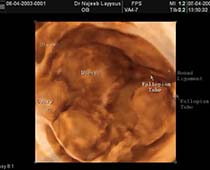

- Laparoscopy Photos 1

- Laparoscopy Photos 2

- Laparoscopy Photos 3

- Laparoscopy Photos 4